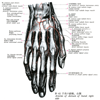

後骨間動脈;背側骨間動脈Posterior interosseous artery(Arteria interossea posterior; Arteria interossea dorsalis)

後骨間動脈;背側骨間動脈【こうこつかんどうみゃく;はいそくこつかんどうみゃく】 Artery passing dorsally between the interosseous membrane of forearm and the oblique cord that supplies the extensor muscles of the forearm, extending as far as the carpal dorsal arch.(後骨間動脈は前腕骨間膜と斜索の間、次いで回外筋と長母指外転筋の間を通って前腕の背面に出て、ここから深筋群の間を下行して、前腕の遠位部で前骨間動脈と吻合して背側手根動脈網をつくる。)